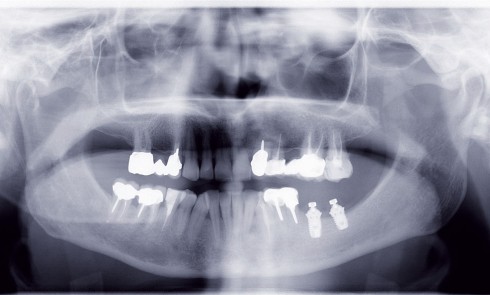

Article réservé à nos abonnés Perte osseuse mandibulaire interruptrice et prothèse amovible implanto-retenue

La mise en œuvre d’une réhabilitation prothétique complète fonctionnelle après chirurgie carcinologique de la mandibule n’est pas toujours aisée, en...